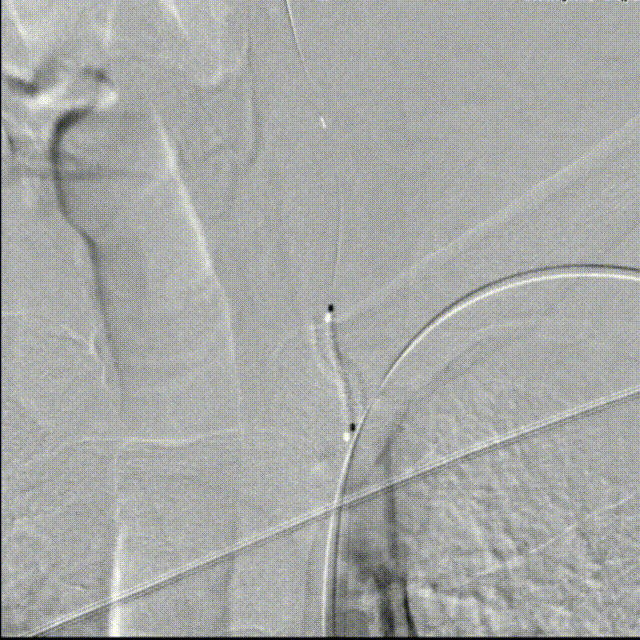

造影见LV闭塞,立即沿0.014*200cm 通桥北斗SS™神经血管导丝置入3mm*16mm 药物球扩支架至LV1。

压力泵逐渐加压球扩支架到8atm, 支架打开良好,造影示残余狭窄0%。

双侧锁骨下动脉造影见椎动脉、基底动脉血流通畅,远端未见栓塞表现。

扩张锁骨下动脉时,预判椎动脉有栓塞风险,椎动脉预留保护导丝通路很重要。

左椎支架开口下端斑块完全覆盖,减少远期再脱落风险。